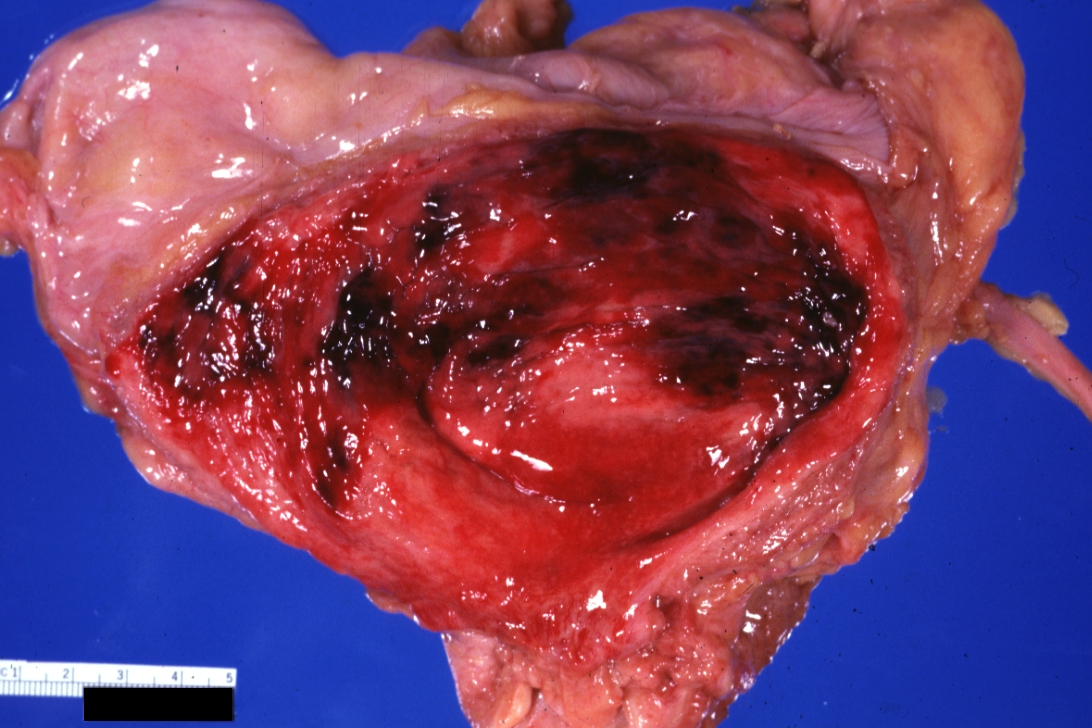

GROSS: Urinary: Bladder: Hemorrhagic Cystitis: Gross natural color typical good photo